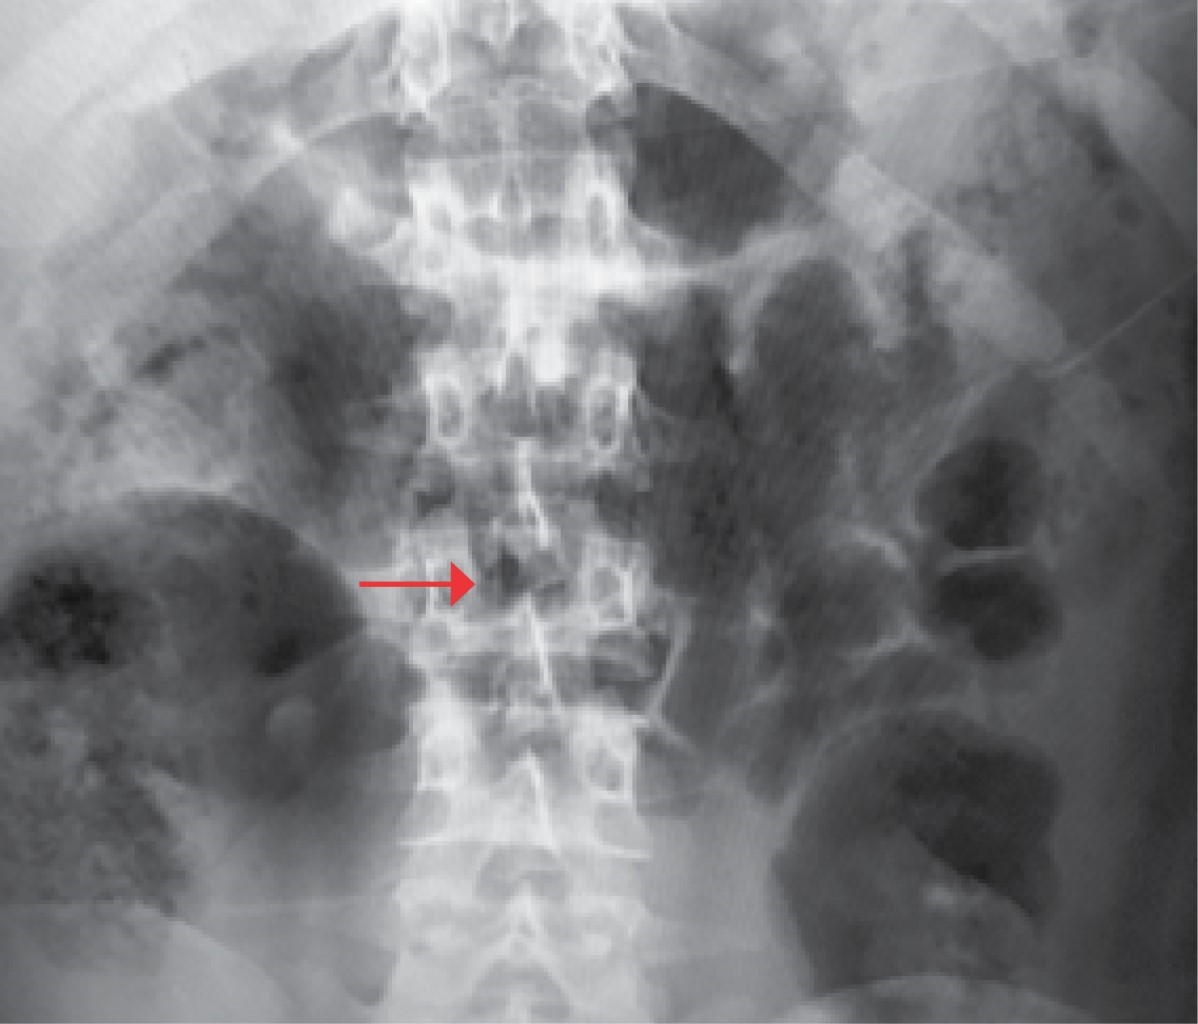

La anestesióloga informó de inmediato a la paciente sobre el incidente que había ocurrido y marcó el área de inserción. En ese momento, la mujer no presentaba ninguno de los síntomas asociados con el fragmento de la aguja que había quedado dentro de su columna, así que se determinó no realizar un examen neurológico, ya que su diagnóstico requería practicarle la cesárea de forma urgente, y así evitar mayores complicaciones del binomio. La anestesióloga y la ginecóloga decidieron continuar con la cirugía, pero cambiaron el procedimiento inicial por la aplicación de anestesia general balanceada, iniciado con tratamiento antiinflamatorio no esteroideo (AINEs), metamizol 2 g en infusión, así como la administración de esteroide, dexametasona 8 mg intravenoso. Por su parte, la paciente se mostró de acuerdo con las especialistas, así que se llevó a cabo la intervención quirúrgica de cesárea y, posteriormente, se le tomó una radiografía de columna anteroposterior y lateral (Figuras 2 y 3). Debido a que el hospital donde se presentó el evento no cuenta con esos recursos, no se realizó otro tipo de estudio como la tomografía axial computarizada y la resonancia magnética. En cuanto se obtuvieron los resultados de las radiografías, se solicitó interconsulta con un médico neurocirujano, quien refirió que tenía que ser intervenida de nueva cuenta. La cirugía se programó y se efectuó de inmediato.

Figura 2